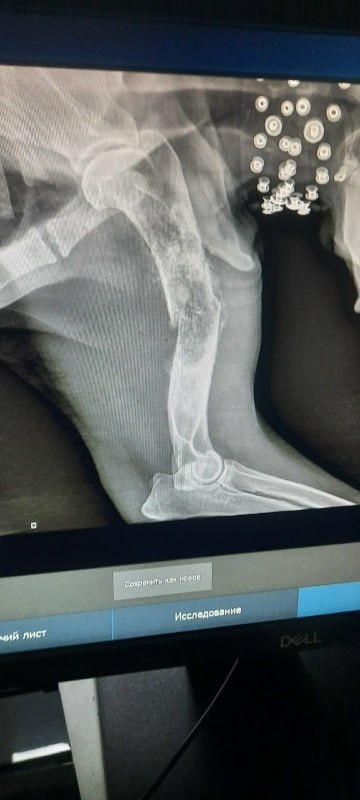

Срочно 🚨 у алабая онкология костей ❗️❗️❗️

КТ нужно делать 20 тыс., опухоль ещё на селезенке, удаление лапы 60 тыс.

К сбору 80 тыс.

Нужно срочно удалять лапу, пока нет метастаз ❗️❗️